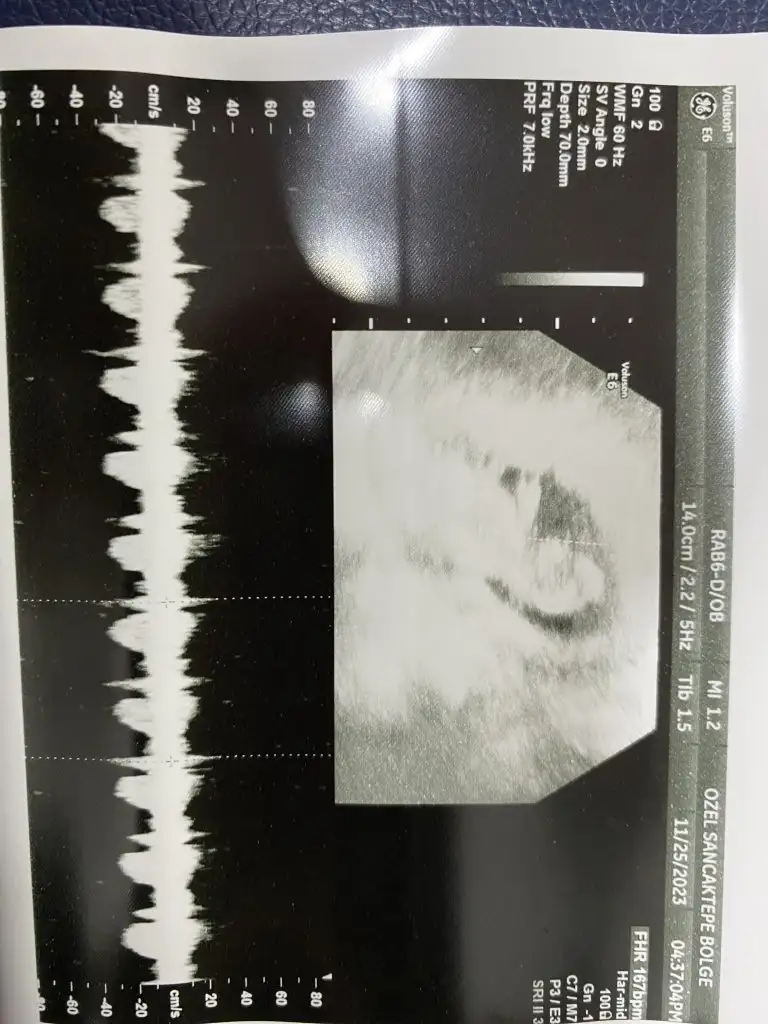

KizBanada tahmin yapar mısınız 13+3

Sizin çok erken ama bazı teorilere göre tahmin yapanlar varmış plesantanin sagindaysa erkek solindaysa kız gibi bilsem yapardimMerhaba bana da yorum yapar mısınız lütfennn vajinal bakıldı 6+3 te